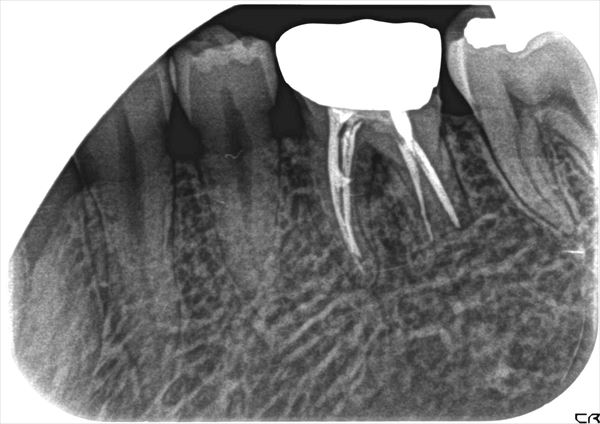

症例4

通常のレントゲン像でも病巣は、なんとなく確認することができますがCTであると、いかに病巣が広範囲に波及しているかがよく判ります。